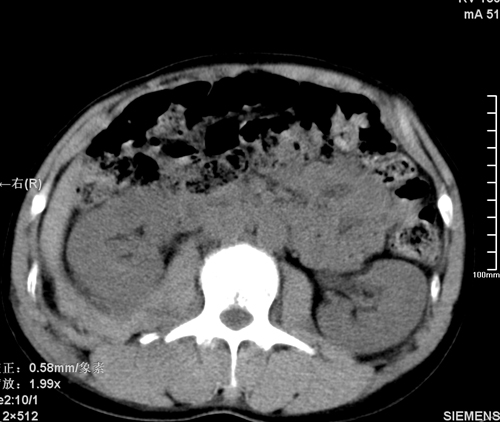

以下是引用tao772在2008-3-28 12:29:00的发言:[br]右侧腹膜后积血,右侧腰大肌挫伤,右侧部分横突骨折. 肾脏最好报一下挫伤,必要时增强。